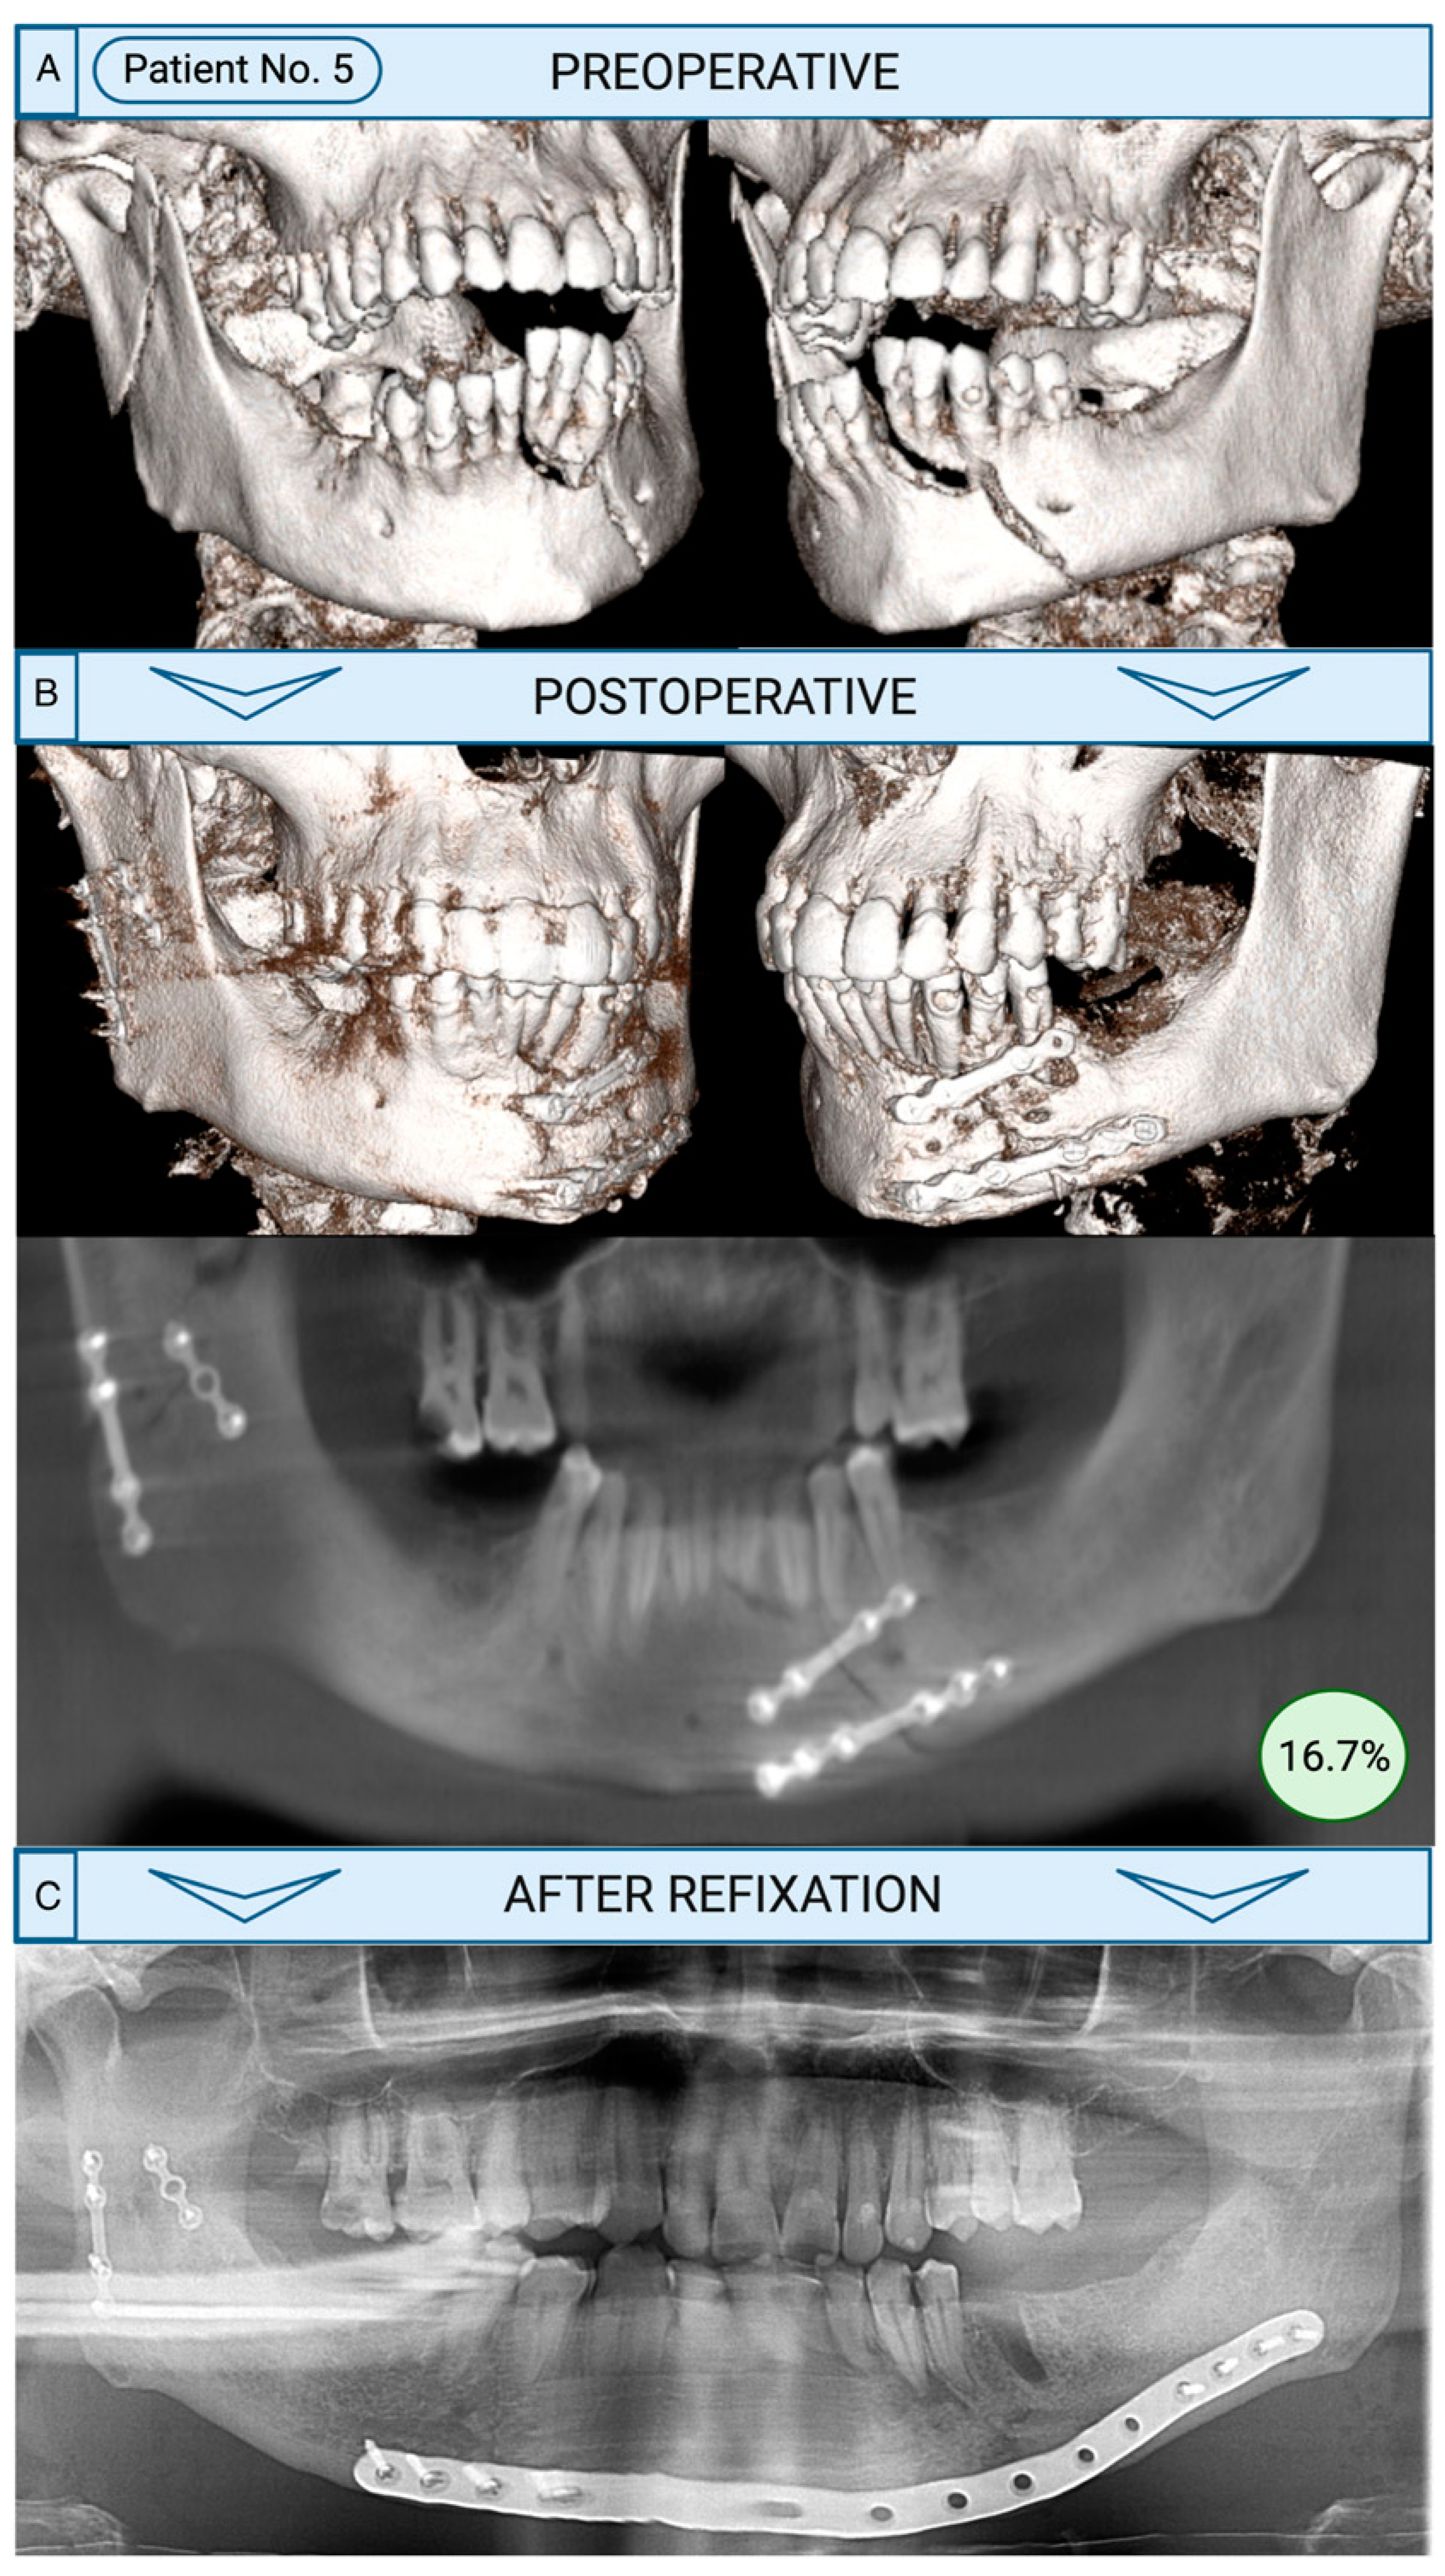

Figure 3. Refixation after development of complications following initial fracture treatment. A: As shown by three-dimensional reconstruction of computed tomography (CT), the initial fracture demonstrated a paramedian left-sided fracture and a right-sided condyle fracture in a male patient with risk factors (smoking + alcohol). B: Postoperative cone-beam computed-tomography (CBCT) showing fracture treatment with miniplate osteosynthesis. One specialist evaluated treatment as insufficient (16.7%). C: The patient developed an osteomyelitis in the paramedian region of the left mandible after 7 months resulting in a refixation using a patient-specific 3D-printed reconstruction plate as demonstrated by the panoramic radiograph. Created with Biorender.com.